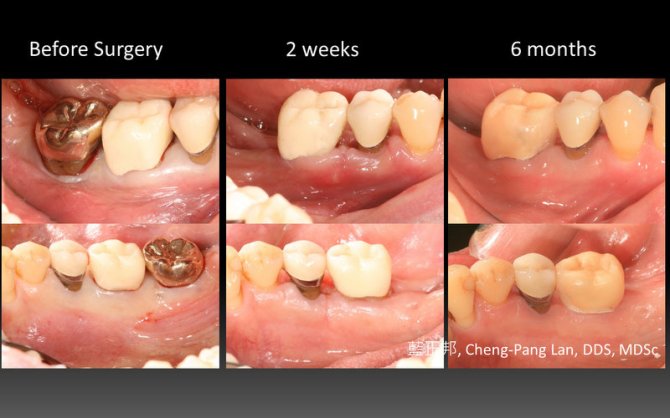

Periodontal Regeneration – Case C